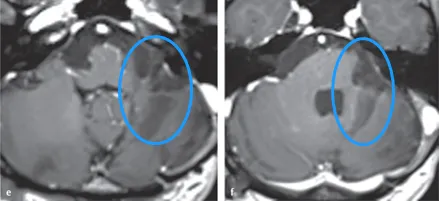

术后病理确诊为胶质母细胞瘤,IDH1与BRAF呈阴性,p53蛋白局部阳性率达50%,O6-甲基鸟嘌呤DNA甲基转移酶(MGMT)启动子高度甲基化。患者按Stupp方案完成放化疗,随访MRI显示残余肿瘤逐渐消退。术后4年随访显示患者可完全独立生活,延髓(图e)与脑桥(图f)轴位T1加权增强MRI未见肿瘤复发征象。